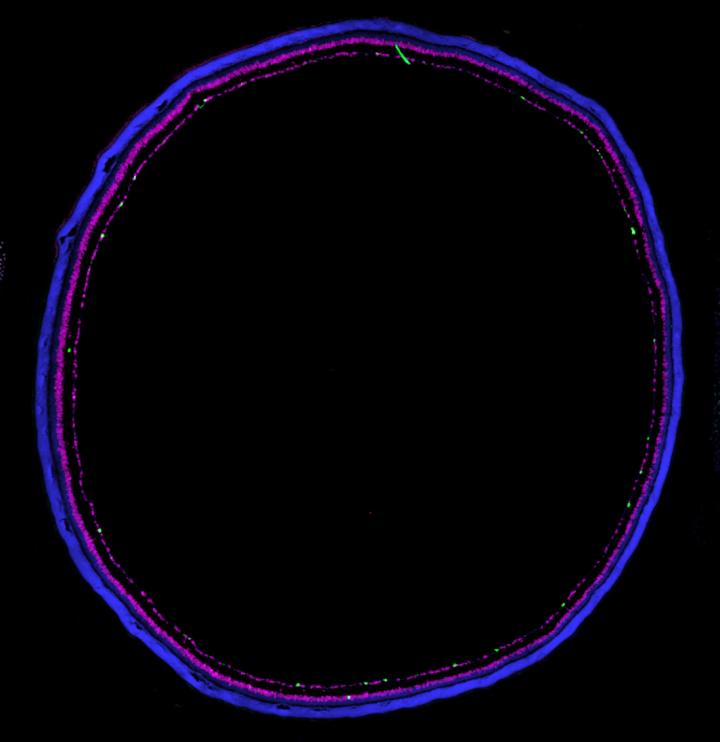

image: Retinal section from a mouse where cell nuclei are labeled in blue, inhibitory cells are labeled with magenta, and ipRGCs are labeled in green.